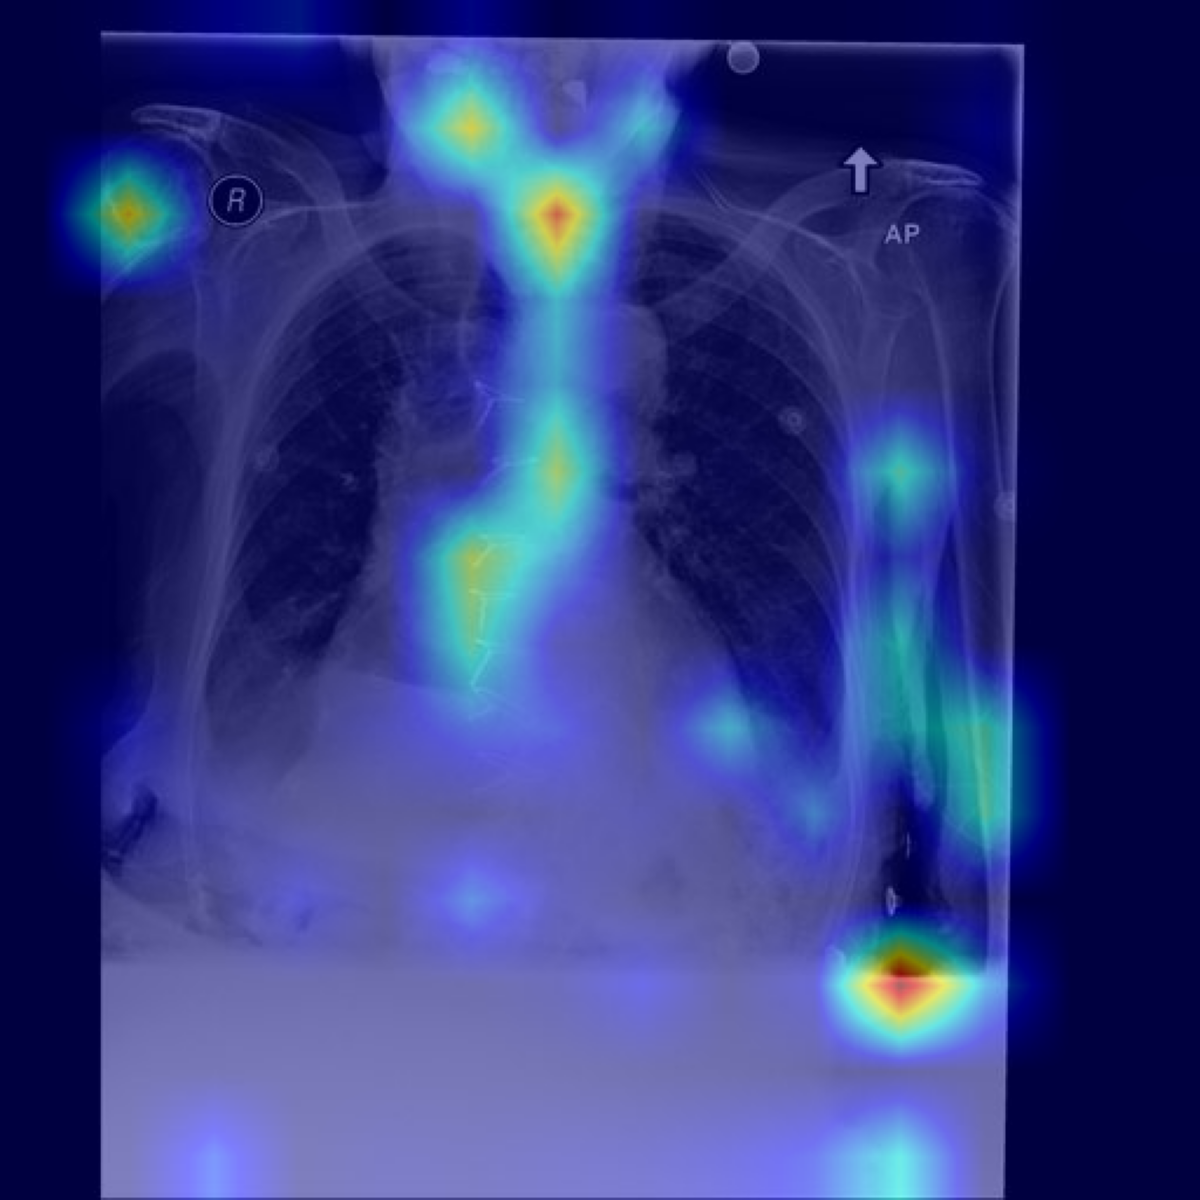

Table 6: Qualitative Examples with Concept-Specific Visual Explanations. Grad-ECLIP heat maps highlight image regions that influence the LLaVA-Med encoder’s matching between input images and SpLiCE concepts (highlighted in blue). The visualizations show which spatial features contribute to concept identification in the generated reports. Top row: Zero-Shot setting; bottom row: supervised fine-tuning setting.

Original Image Grad-ECLIP Activation Maps [Uncaptioned image] [Uncaptioned image] [Uncaptioned image] Endotracheal Tube Right Upper

Original Image Grad-ECLIP Activation Maps [Uncaptioned image] [Uncaptioned image] [Uncaptioned image] Median Sternotomy Bilateral Pleural

For each case, we select SpLiCE concepts that appear in the generated report (e.g., endotracheal tube, right upper, median sternotomy, bilateral pleural). We apply Grad-ECLIP [57] to compute the gradient of the image–text similarity score with respect to the visual features used by the LLaVA-Med vision encoder. The resulting relevance map is then upsampled and overlaid on the chest X-ray as a heat map, yielding a concept-specific visualization of which regions support that term. CEMRAG-generated reports and their corresponding concept heat maps are illustrated in Table 6 for two representative MIMIC-CXR cases, one in the Zero-shot regime and one after SFT. In each example, the left column shows the reference report, while the right column shows the CEMRAG output with the relevant concept tokens highlighted. Below these reports, we display the original image together with Grad-ECLIP maps for two selected concepts. In the Zero-shot example, concepts such as endotracheal tube and right upper are both present in the generated report and exhibit Grad-ECLIP activations that concentrate along the tracheal tube and in the right upper lung zone, respectively. In the SFT example, the concept median sternotomy yields strong activation along the midline sternal wires and retrosternal region, while bilateral pleural produces strongest activation in the lower lung zones near the right and left costophrenic angles, where pleural effusions typically accumulate. Taken together, these patterns are consistent with standard radiological practice and suggest that, when a concept appears in the report, it is usually backed by visually plausible evidence in the corresponding image regions.

These concept-specific maps serve two complementary purposes. First, they allow clinicians to verify that SpLiCE-derived concepts, when injected into the prompt, are grounded in image regions that are consistent with their radiological meaning, rather than reflecting arbitrary directions in embedding space. Second, they expose failure modes in a transparent way: if a concept is mentioned in the report but its Grad-ECLIP map does not align with plausible anatomy, this discrepancy can be inspected, questioned, and potentially used to flag low-trust outputs. At the same time, this analysis remains focused on the vision component: Grad-ECLIP explains how visual encoders support individual concepts, but does not by itself reveal how the LLM composes multiple concepts into full sentences. Extending concept-level tracing to the language component remains an important direction for future work toward fully interpretable medical VLMs.